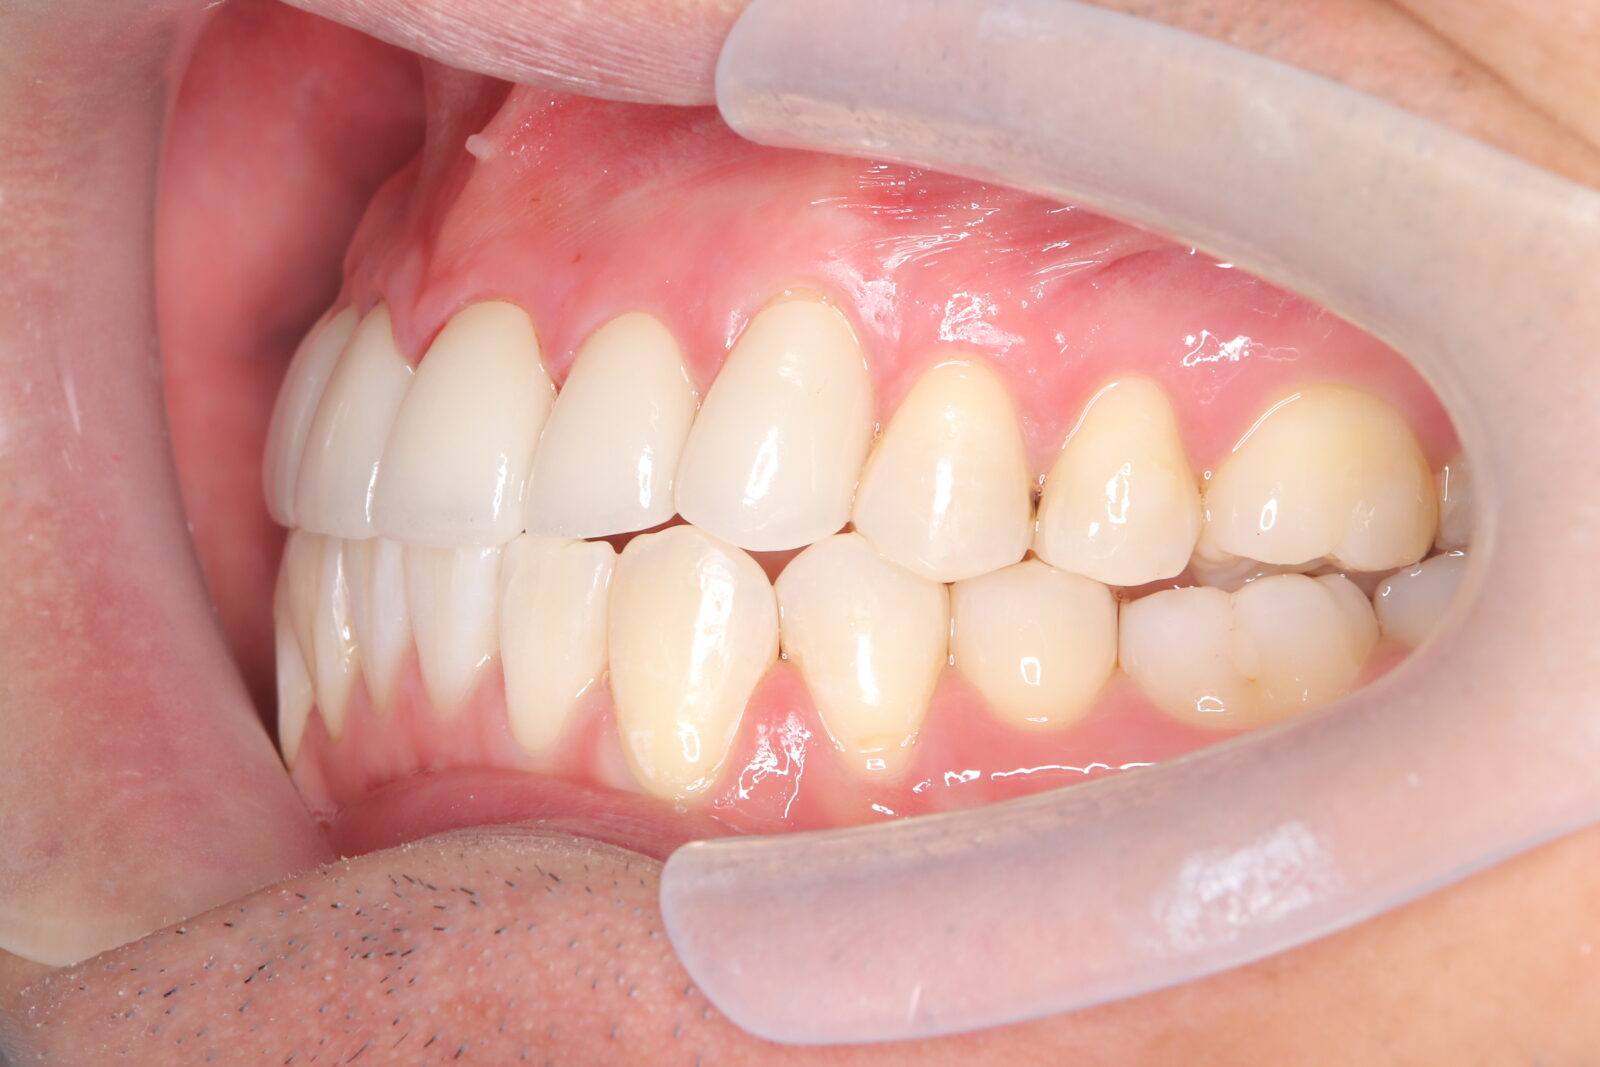

インビザライン(全体矯正)+ホワイトニングコースの症例

典型的な出っ歯だったが、インビザラインとホワイトニングでコンプレックスを改善。

・費用:935,000円(税込)

・治療期間:14ヶ月

・通院回数:14回

・34歳女性

-リスクと副作用-

・長時間マウスピースを装着するため、むし歯や歯周病のリスクがある。治療後はリテーナーを装着しないと後戻りしてしまうリスクがある。

・ホワイトニング剤の影響で知覚過敏が起こる可能性がある。色が徐々に戻る可能性がる。